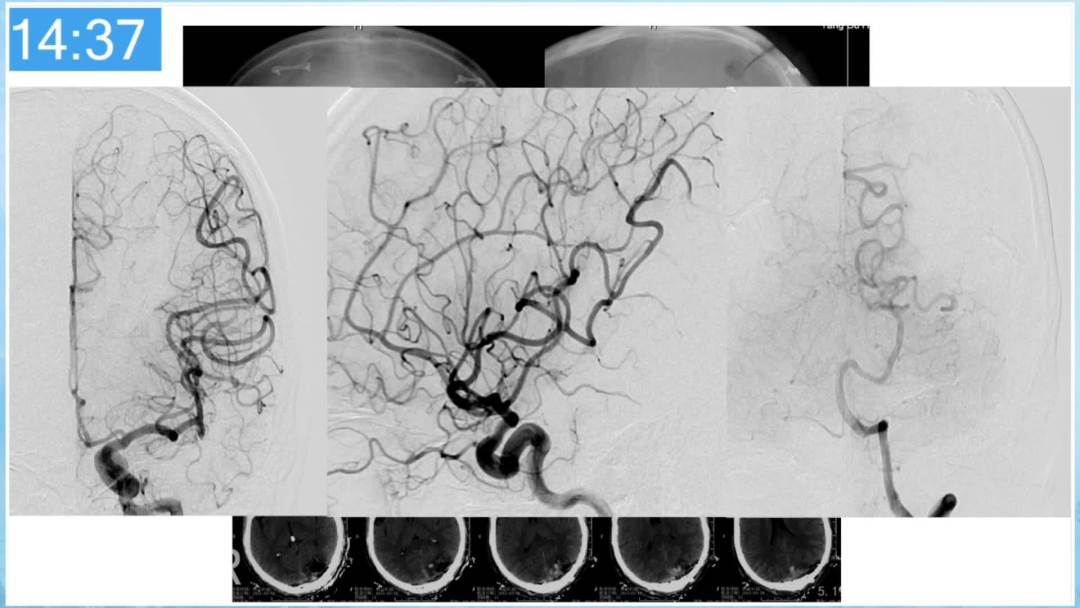

本期为大家特别分享:空军军医大学唐都医院邓剑平教授的精彩会议内容《颅内动静脉畸形的复合手术治疗》,欢迎大家阅读和分享!